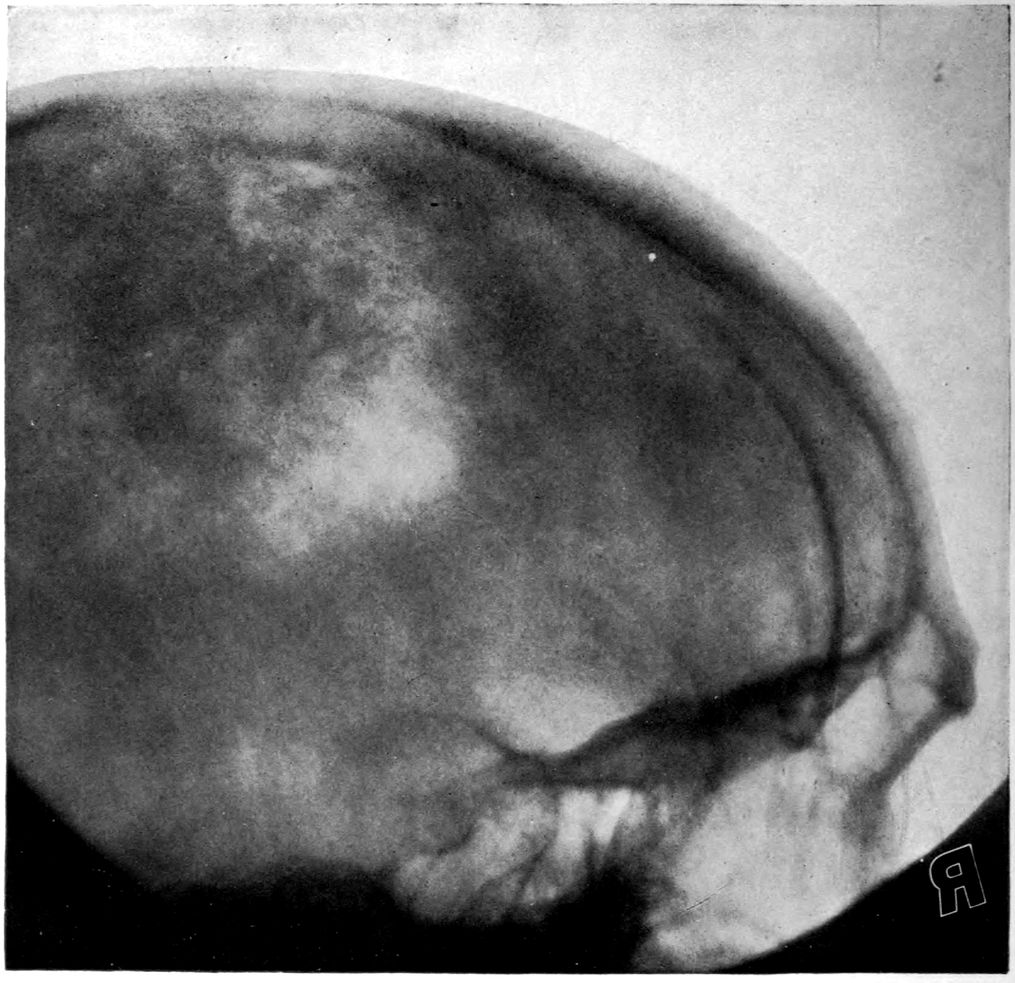

Vascular neurosyphilis—effects of syphilitic thrombosis of Sylvian artery 10 years before death. (Case 4.)

Case 4. James Pierce was an almshouse transfer to the Danvers Hospital in his fiftieth year. He died three years later. The accompanying brain pictures demonstrate so extensive a lesion of the left hemisphere that it is of great interest to determine if possible the genesis and course of his disease. It appears that syphilis had been acquired somewhere about the age of 38 or 40, so that the total duration of the process was between 13 and 15 years. In Pierce’s forty-third or forty-fourth year, he had a shock while walking in the streets of his native city, whereupon he was subsequently transferred to the Danvers Hospital, whose data have been summed up as follows (we are obliged to Dr. Charles T. Ryder for these data):

Head: Calvarium of moderate thickness; diploë present; dura slightly adherent over bregmatic region. Longitudinal sinus contains cruor clot. Dura is somewhat thickened and slightly more opaque than normal. Pacchionian granulations, small but fairly numerous. Pia contains throughout a considerable excess of clear 44serous fluid. The convolutions in general are of good breadth and proportion. There is an atrophic area roughly circular in outline and about 2 cm. in diameter in the posterior part of the right third frontal convolution corresponding to Broca’s area on the opposite hemisphere. The space thus formed is filled with edema held by the pia. On the left side is a similar subpial collection which covers the site of the posterior portions of all of the third frontal convolutions, parts of the lower end of the precentral convolution, and the whole of the first temporal convolution, which have disappeared entirely. The basal vessels show slight changes.